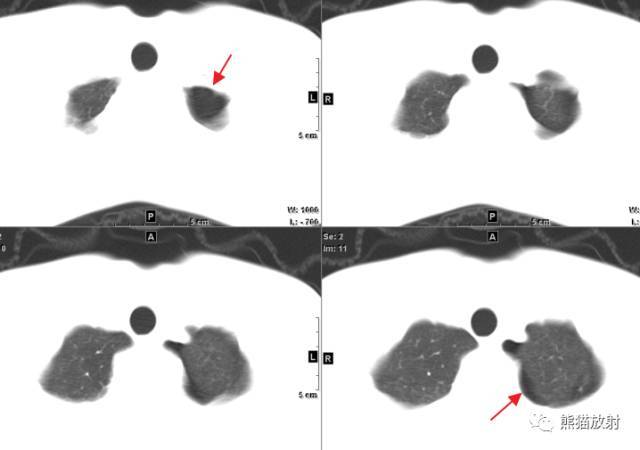

左侧气胸(肺被压缩约40%):

左侧胸腔可见移位的胸膜线影 , 其外侧为条带状无纹理区 , 宽度小于患侧胸廓的1/3 。